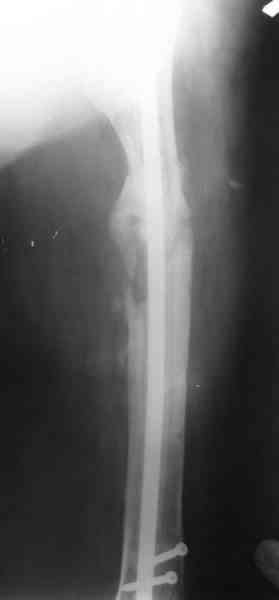

1, 2, 3, 4 - рентгенограммы бедра от 8 августа этого года (через четыре месяца после операции);

В настоящее время наш пациент ( см. http://weborto.net/forum/1177351385/) ходит с одним костылем. У него периодически открывается свищ на задне-наружной поверхности бедра с умеренным серозно-гнойным отделяемым. Температура тела и анализы нормальные. На рентгенограммах имеются признаки консолидации ложного сустава.